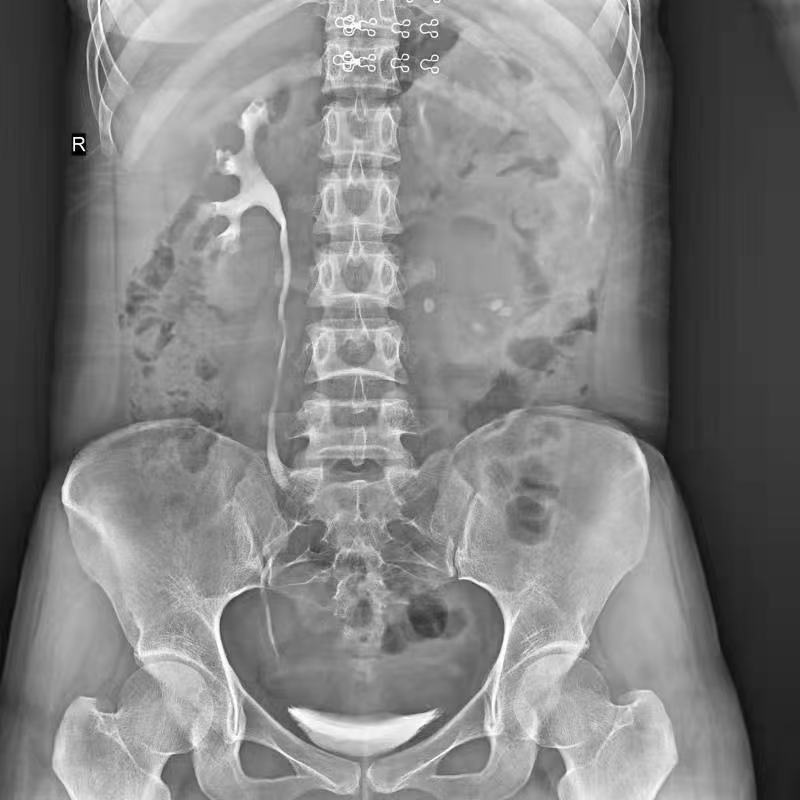

普利德醫(yī)療自主研發(fā)的新一代數(shù)字化X線透視攝影系統(tǒng),可應(yīng)用于DR攝影、數(shù)字透視、數(shù)字造影以及可視化精準(zhǔn)DR拍片等多種臨床X線檢查領(lǐng)域。

● 獨(dú)特實(shí)用的床面升降功能,有利于DR攝影及行動(dòng)不便的患者上下床;

● 床面可降至與病床平行高度,既方便醫(yī)護(hù)人員平移患者,又避免對(duì)患者的二次傷害;

● 對(duì)于醫(yī)生的近臺(tái)操作也更方便,不同身高的醫(yī)生可根據(jù)需要調(diào)節(jié)床體高度,更利于醫(yī)生開(kāi)展相關(guān)近臺(tái)手術(shù)。